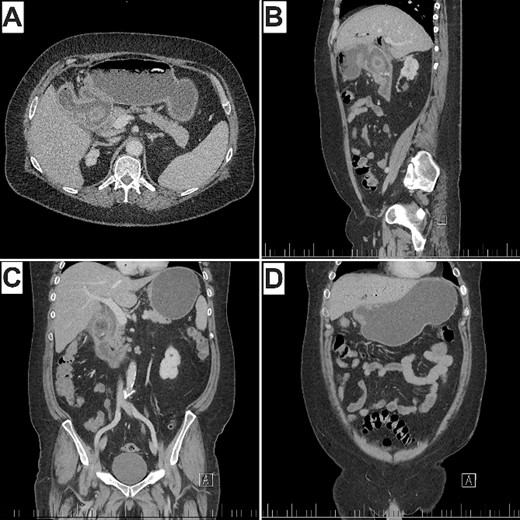

A 64-year-old male presented with a 1-month history of epigastric pain that had acutely worsened in the 3 days prior with fevers, anorexia, and multiple vomits. This was on a background of type 2 diabetes mellitus and hypertension. An abdominal CT, 4 years prior incidentally demonstrated multiple dependent calculi in the gallbladder, the largest measuring 23 × 23 mm. On examination, he was haemodynamically stable and afebrile. His abdomen was soft although tender in the right upper quadrant. Murphy’s sign was positive. Routine biochemistry revealed mildly elevated inflammatory markers and alkaline phosphatase (Table 1). CT of the abdomen and pelvis revealed the known gallstone, now 28 mm in diameter, had dislodged and impacted between the first and second parts of the duodenum through a cholecystoduodenal fistula. There was associated gastric distension, pericholecystic inflammatory stranding, and pneumobilia (Fig. 1). These findings satisfy Rigler’s triad of an ectopic gallstone, gastric outlet obstruction, and pneumobilia. Accordingly, a diagnosis of Bouveret syndrome was made.

CT of the abdomen and pelvis (A) axial, demonstrating pneumobilia, cholecystoduodenal fistula, and impacted gallstone. (B) Sagittal, (C) coronal, demonstrating obstructing gallstone in the proximal duodenum with distal duodenal collapse and pericholecystic inflammatory stranding. (D) Gastric distension proximal to the impacted stone. Note Rigler’s triad of pneumobilia (A), ectopic gallstone (A, B, C), and gastric outlet obstruction (B, D).

Of note in this case is the prompt diagnosis of Bouveret syndrome just hours following presentation, owing to CT imaging. The scan promptly demonstrated Rigler’s triad; pneumobilia, ectopic gallstone, and gastric outlet obstruction (Fig. 1), pathognomonic for Bouveret syndrome [4]. A limitation of CT, however, is its inability to detect iso-attenuating stones, the scenario in ~15% to 25% of cases [4]. In these situations, magnetic resonance cholangiopancreatography may be considered.